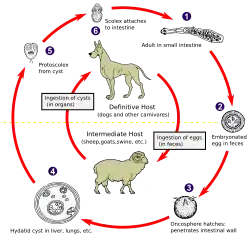

| Echinococcus granulosa life cycle (click to enlarge) | |

Life cycle

An adult worm resides in the small intestine of a definitive host. A single gravid proglottid releases eggs that are passed in the feces of the definitive host. The egg is then ingested by an intermediate host. The egg then hatches in the small intestine of the intermediate host and releases an oncosphere that penetrates the intestinal wall and moves through the circulatory system into different organs, in particular the liver and lungs. Once it has invaded these organs, the oncosphere develops into a cyst. The cyst then slowly enlarges, creating protoscolices (juvenile scolices), and daughter cysts within the cyst. The definitive host then becomes infected after ingesting the cyst-containing organs of the infected intermediate host. After ingestion, the protoscolices attach to the intestine. They then develop into adult worms and the cycle starts all over again.[23]

Eggs

Echinococcus eggs contain an embryo that is called an oncosphere or hexcanth. The name of this embryo stems from the fact that these embryos have six hooklets. The eggs are passed through the feces of the definitive host and it is the ingestion of these eggs that lead to infection in the intermediate host.[24]

Larval/hydatid cyst stage

From the embryo released from an egg develops a hydatid cyst, which grows to about 5–10 cm within the first year and is able to survive within organs for years.[25] Cysts sometimes grow to be so large that by the end of several years or even decades, they can contain several liters of fluid. Once a cyst has reached a diameter of 1 cm, its wall differentiates into a thick outer, non-cellular membrane, which covers the thin germinal epithelium. From this epithelium, cells begin to grow within the cyst. These cells then become vacuolated, and are known as brood capsules, which are the parts of the parasite from which protoscolices bud. Often, daughter cysts also form within cysts.[24]

Adult worm

Echinococcus adult worms develop from protoscolices and are typically 6 mm or less in length and have a scolex, neck and typically three proglottids, one of which is immature, another of which is mature and the third of which is gravid (or containing eggs).[24] The scolex of the adult worm contains four suckers and a rostellum that has about 25–50 hooks.[26]

Morphological differences

The major morphological difference among different species of Echinococcus is the length of the tapeworm. E. granulosus is approximately 2 to 7 mm while E. multilocularis is often smaller and is 4 mm or less.[19] On the other hand, E. vogeli is found to be up to 5.6 mm long and E. oligarthrus is found to be up to 2.9 mm long.[21] In addition to the difference in length, there are also differences in the hydatid cysts of the different species. For instance, in E. multilocularis, the cysts have an ultra thin limiting membrane and the germinal epithelium may bud externally. Furthermore, E. granulosus cysts are unilocular and full of fluid while E. multilocularis cysts contain little fluid and are multilocular. For E. vogeli, its hydatid cysts are large and are actually polycystic since the germinal membrane of the hydatid cyst actually proliferates both inward, to create septa that divide the hydatid into sections, and outward, to create new cysts. Like E. granulosus cysts, E. vogeli cysts are filled with fluid.[24]

Transmission

As one can see from the life cycles illustrated above, all disease-causing species of Echinococcus are transmitted to intermediate hosts via the ingestion of eggs and are transmitted to definitive hosts by means of eating infected, cyst-containing organs. Humans are accidental intermediate hosts that become infected by handling soil, dirt or animal hair that contains eggs.[19]